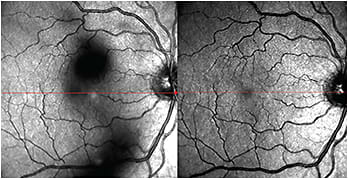

The entopic sensation of floaters (Figure), the gray patches that may temporarily obscure vision, can affect perceived quality of life in some individuals. Vitreous collagen reorganization and liquefaction (which occur in all individuals over time) results in aggregation of collagen fibrils, liquefaction of the gel (vitreous synchysis), and collapse (vitreous syneresis) of vitreous “away” from the retina (posterior vitreous detachment).1

Figure. Scanning laser ophthalmoscope image (left) of focal floaters in the right eye. When these floaters enter the optical axis, degradation of contrast sensitivity occurs due to light scattering. Postoperative SLO (right) demonstrates clearing of floaters after minimally invasive vitrectomy.

COURTESY: J. SEBAG, MD